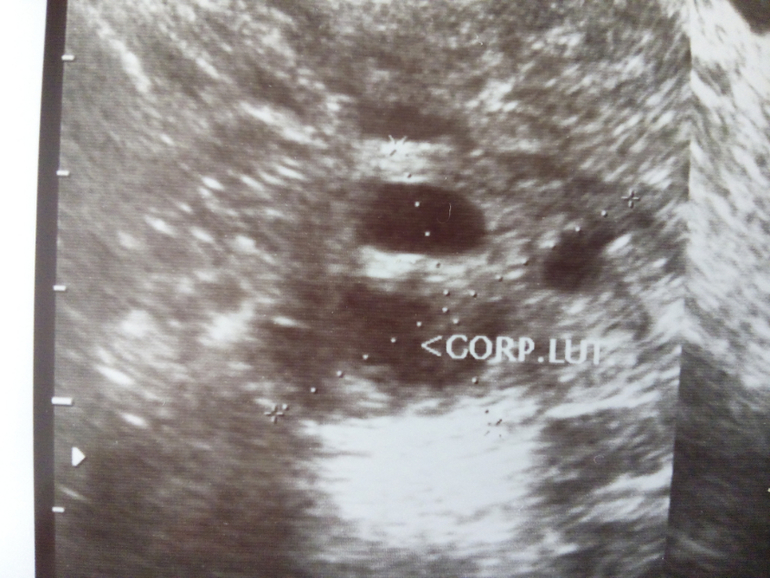

Базальная температура, ТТ, графики БТВ этом цикле О отслеживала тестами ,графиком БТ,и УЗИ.Овуляция была ранняя на 13 дц(как сказал врач на узи),и тесты среагировали в эти дни.НО! БТ не хочет подниматься,я в шоке!!!К врачу своему идти не хочу,она,мягко говоря ...,короче ничего не знает.Что делать???Я переживаю ещё вот по какому поводу:жидкости в позамоточном пространстве не было,может это не ЖТ,а киста какая нибудь,и из-за этого БТ не растёт?

Узи и график выкладываю,кто понимает,может подскажите?